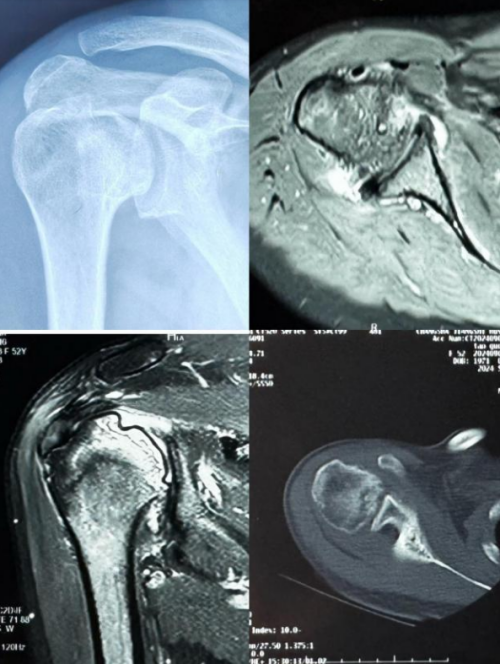

经人推荐,李阿姨慕名来到91短视频 运动医学、创伤、关节、骨病科丑克主任专家门诊就诊,检查发现右三角肌、斜方肌、冈下肌、小圆肌萎缩,右侧肱骨头坏死,核磁共振检查显示肱骨头软骨下骨囊性变,肱骨头塌陷。丑克建议李阿姨行肩关节置换,随后入院治疗。

患者术前评估:右上肢无法正常上抬

术前影像检查显示肱骨头软骨下骨囊性变,肱骨头塌陷